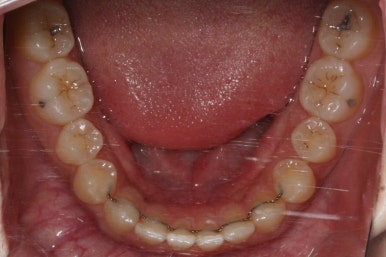

위 사진은 부산치아교정치과에 내원하셨을 대 당시의 입안 모습입니다.

치아들 사이에 전반적으로 틈이 많이 있는 상태입니다.